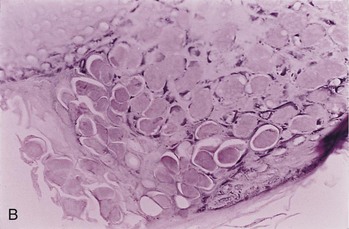

image image

Figure 52-7 Molluscum contagiosum. A, Skin lesions. B, Microscopic view; epidermis is filled with molluscum bodies (magnification 100×).

The diagnosis of molluscum contagiosum is confirmed histologically by the finding of characteristic large, eosinophilic, cytoplasmic inclusions (molluscum bodies) in epithelial cells (Figure 52-7B). These bodies can be seen in biopsy specimens or in the expressed caseous core of a nodule. The molluscum contagiosum virus cannot be grown in tissue culture or animal models.